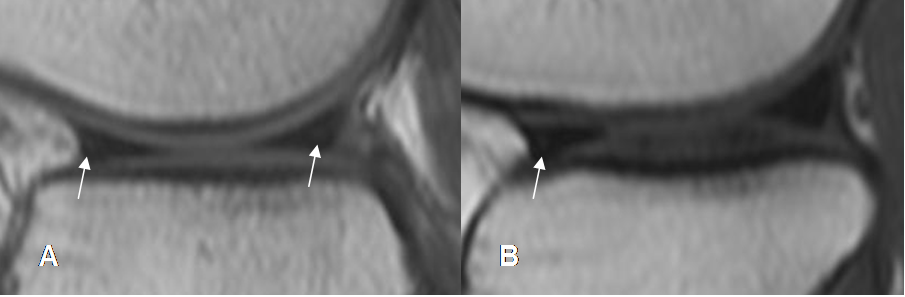

Fig 68. Ruptura meniscal dudosa.

A y B: RM sagital en T1. Imágenes hiperintensas y en sentido oblicuo, sobre el cuerno posterior del menisco interno. La completa comunicación con el borde inferior, es difícil de determinar con certeza.